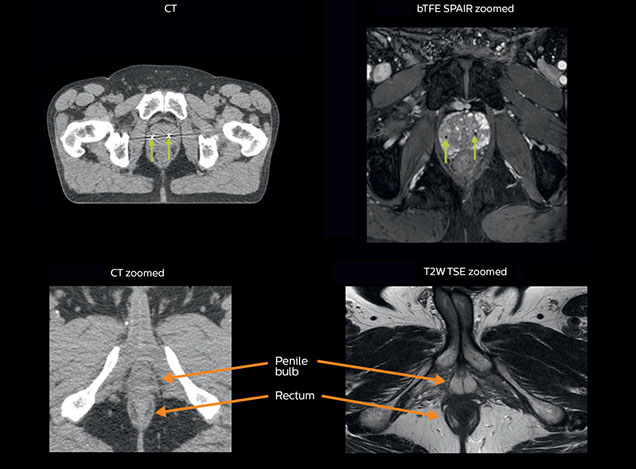

MRI is capable of visualizing the prostate and the surrounding organs such as rectum, penile bulb, bladder, the apex and seminal vesicles, as well as visualizing intra-prostatic lesions [2,4].

“All our patients undergo an MRI exam – along with CT – before radiotherapy of the prostate,” says Dr. Philippens. “For prostate delineation, we are scanning a balanced TFE with fat suppression. We can also see the gold fiducial markers in these images, which are used for position verification and are therefore used for registration to CT. For geometric accuracy of the image, we choose a 3D sequence, which is corrected for the gradient non-linearities in all directions.

Intraprostatic lesions are visible on the bTFE MR image, but not on the CT image. MRI shows excellent soft-tissue contrast for the visualization of critical structures like the rectum and penile bulb.

Fiducial markers (green arrows) are used in registration of MR images to CT, to transfer the MR-based delineations onto the CT image dataset.